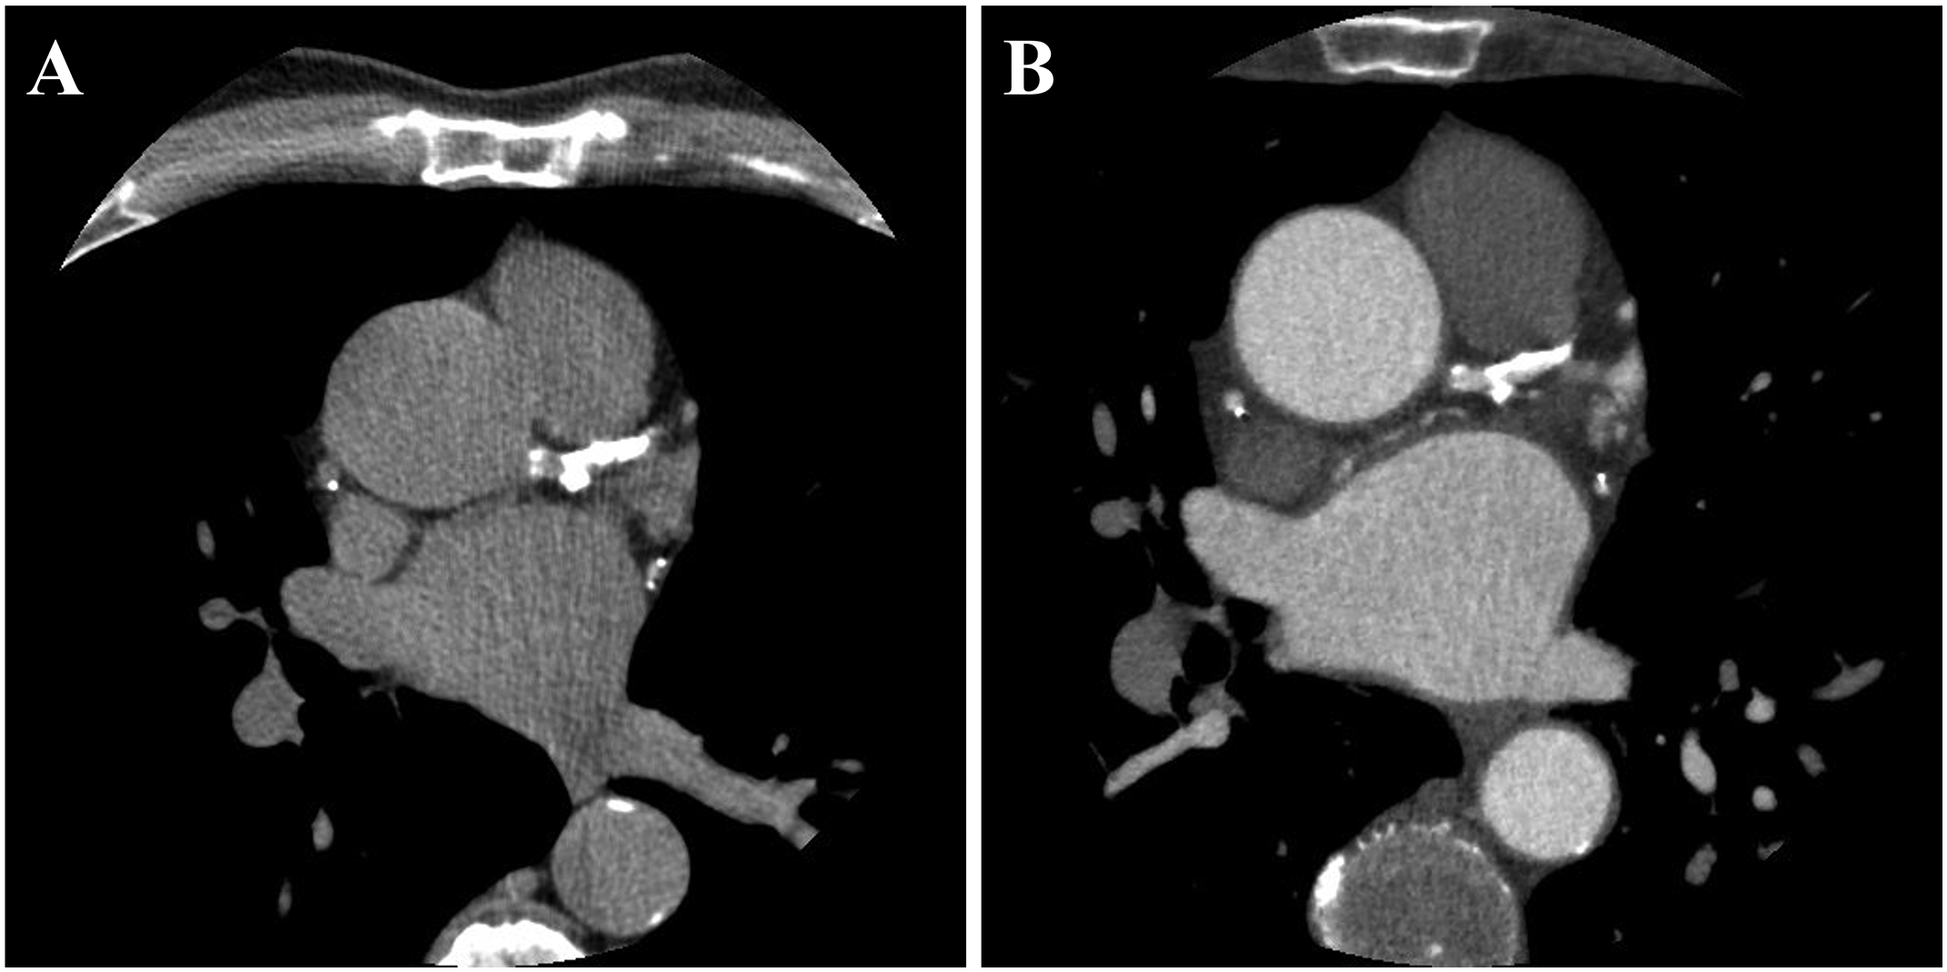

The assessment of positive remodeling for each coronary segment was conducted using standardized semi-automated software (Autoplaque, Version 2.5, Cedars-Sinai Medical Center). PR was characterized by an outer vessel diameter that was at least 10% greater than the average diameter of the segments directly proximal and distal to the plaque (remodeling index >1.1) (17). The remodeling index was calculated by semi-automatically extracting coronary artery centerlines and identifying the vessel lumen, wall, and plaque components on multi-planar reformatted images, with manual adjustments as necessary. Subsequently, the vessel diameters were measured to determine the remodeling index. In this study, PR was evaluated in the proximal, mid, and distal regions of each major coronary artery, including the left anterior descending (LAD), left circumflex (LCX), and right coronary artery (RCA). A patient was considered to have PR if at least one PR was present in any of these arteries. The reliability of observer agreement in assessing positive remodeling has generally been reported as fair (18). Figure 1 illustrates an example of paired CTCS and CCTA images showing PR in the left anterior descending artery.

Figure 1

A representative example of paired CTCS (A) and CCTA (B) images showing the presence of PR. PR was observed in all major coronary arteries, including the left anterior descending (LAD), left circumflex (LCX), and right coronary artery (RCA). The total Agatston score was 3,027, distributed as follows: left main, 43; LAD, 1,168; LCX, 633; and RCA, 1,183.